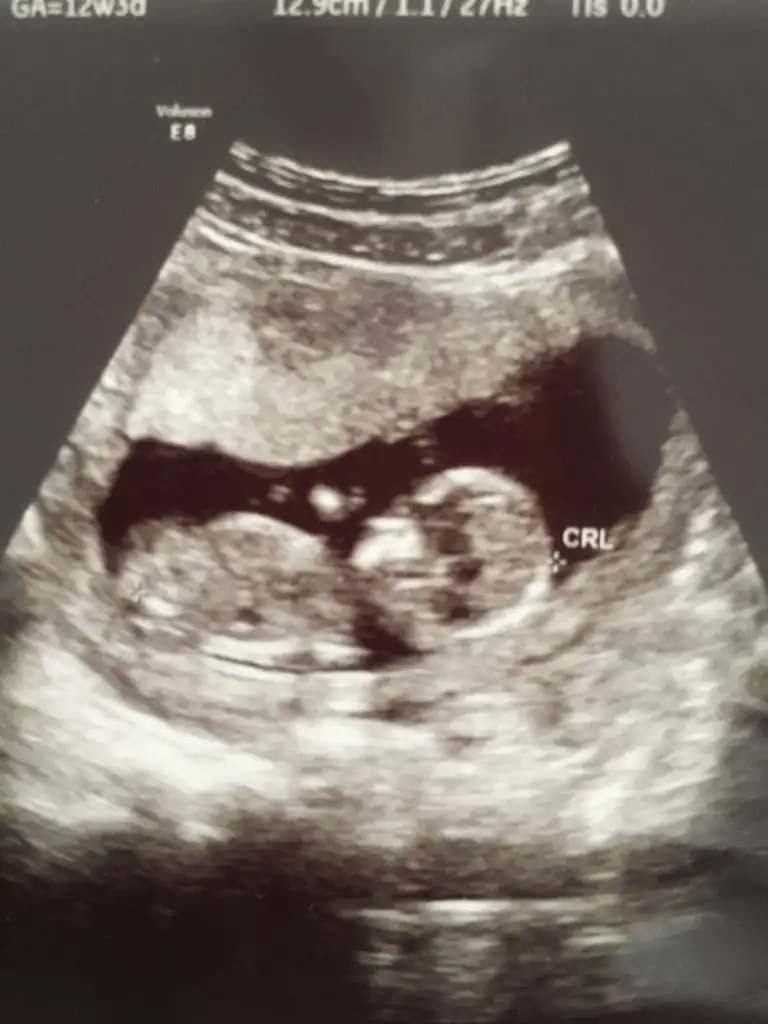

Erkek gibi sanki başka usgde paylasin

Amin çok teşekkür ederimikra hanım daha iyi bakar ama sanki ben erkek nub gördüm sağlıkla gelsin inş

1 hafta sonra gideceğim paylaşacağım çok teşekkür ederim AblacığımErkek gibi sanki başka usgde paylasin

Evet canım sende erkeğe benzetmiştin

Sağlıkla gelsin oğlusunEvet canım sende erkeğe benzetmiştinTeşekkür ederim

Başka USG varsa paylaşın emin olamadım sanki kız gibi 11 12 13 haftalar olmalı 14 değil renkle oynadım emin olmak için ama emin değilim tİkra meyra cnm bunuda bakarmısın 14haftalık

Şimdilik erkek yönünde ama en iyi 11 12 13 haftalar olmalıRica etsem bize de bakar mısınızburada 10+4

Sanki erkek gibi